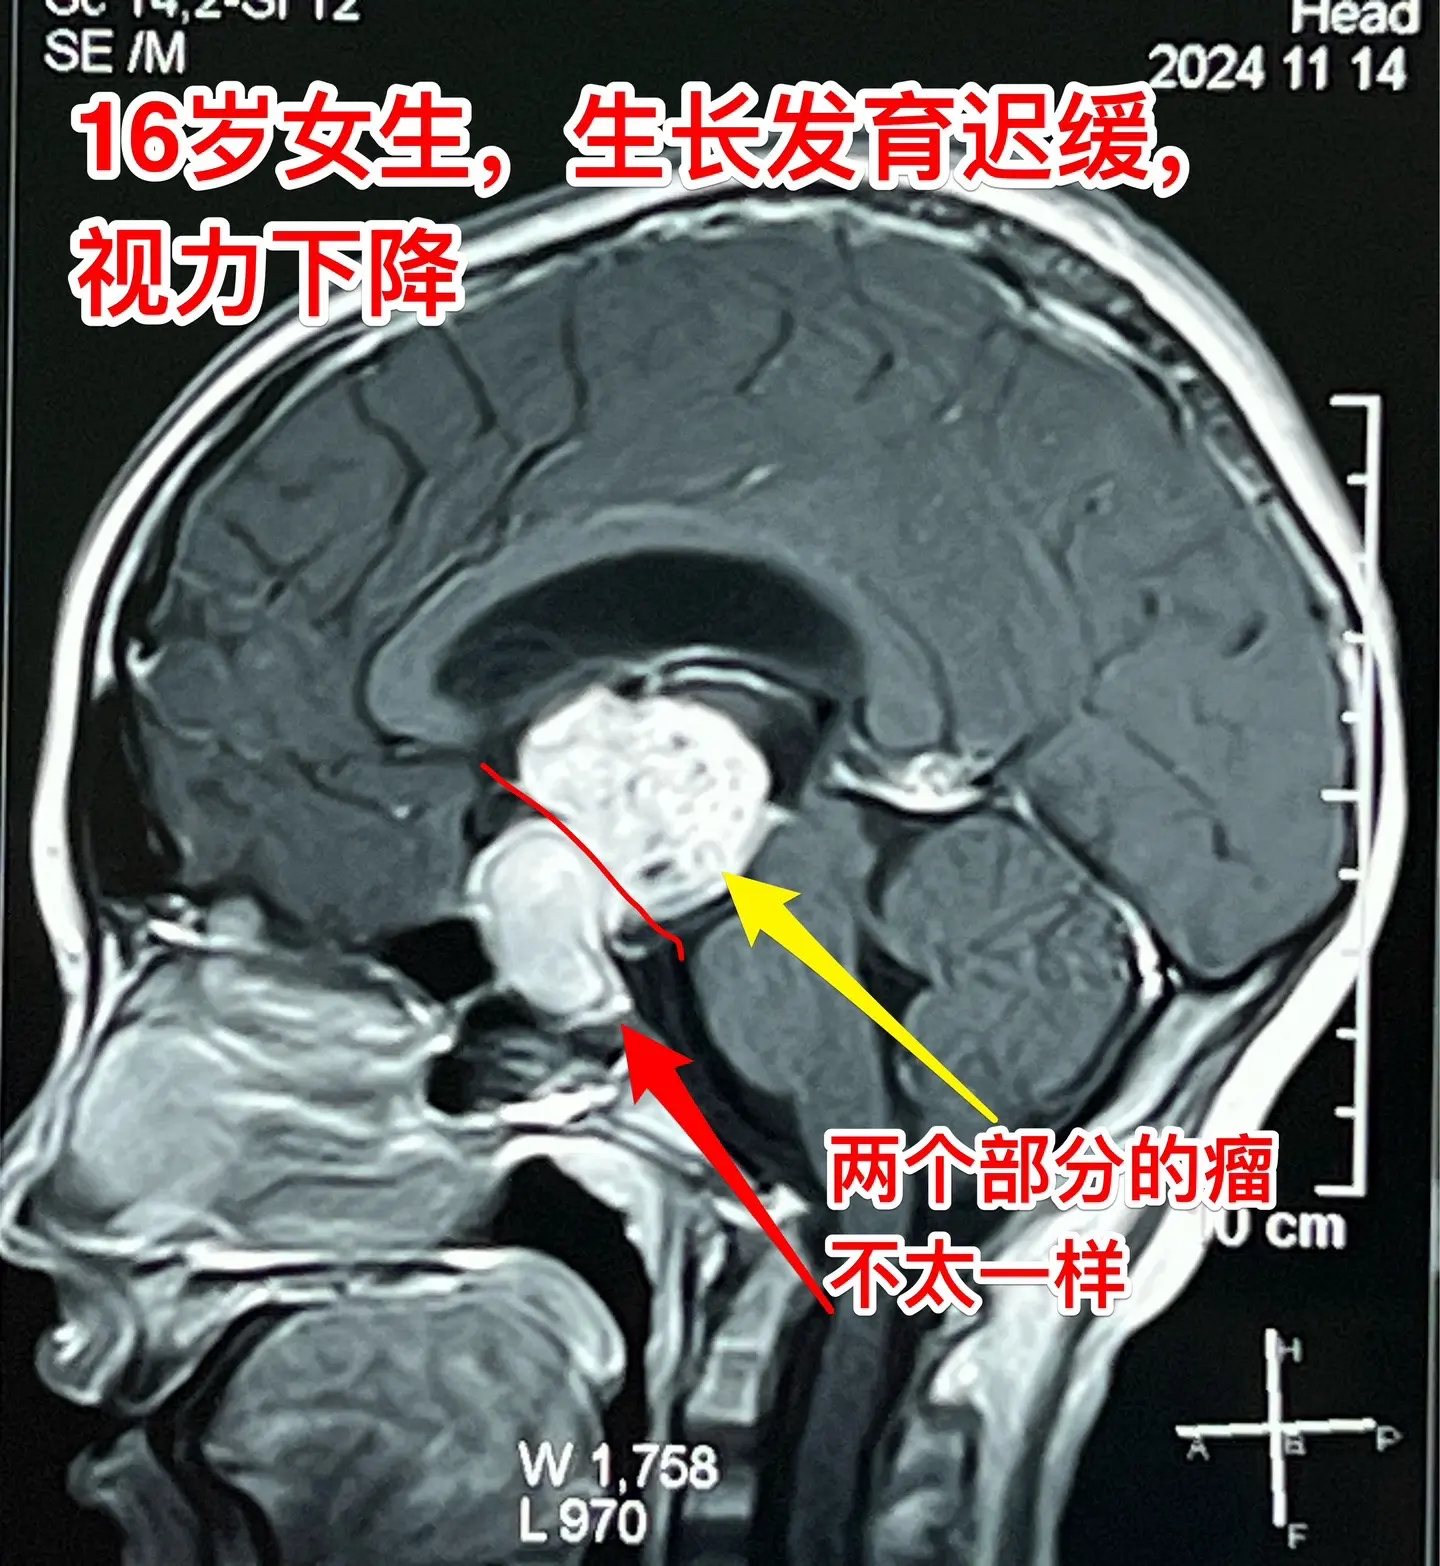

16岁女生在10岁时就有生长发育迟缓症状。16岁衡阳市女生,现在身高才120厘米,体重才21公斤。初中毕业后就辍学了! 她在10岁时就有生长发育迟缓症状,到医院去检查发现生长激素分泌不足。没有找出具体原因,也没有注射生长激素治疗。 近一年有头痛症状,视力也下降了。作磁共振发现长了脑部肿瘤,才到北京来找我作手术。肿瘤体积大,没有钙化,是颅咽管瘤吗? 昨天在手术过程中,取出病变标本作快速冰冻病理检查,报告为乳头型颅咽管瘤。这种类型的颅咽管瘤在小孩子中十分罕见。 我多次提醒家长,如果发现小孩子的生长发育有异常,要尽早到医院去检查,找出原因,尤其是针对脑部要作磁共振检查,排除脑部肿瘤。对于生长激素缺乏者,不能不管原因,轻易注射生长激素治疗。